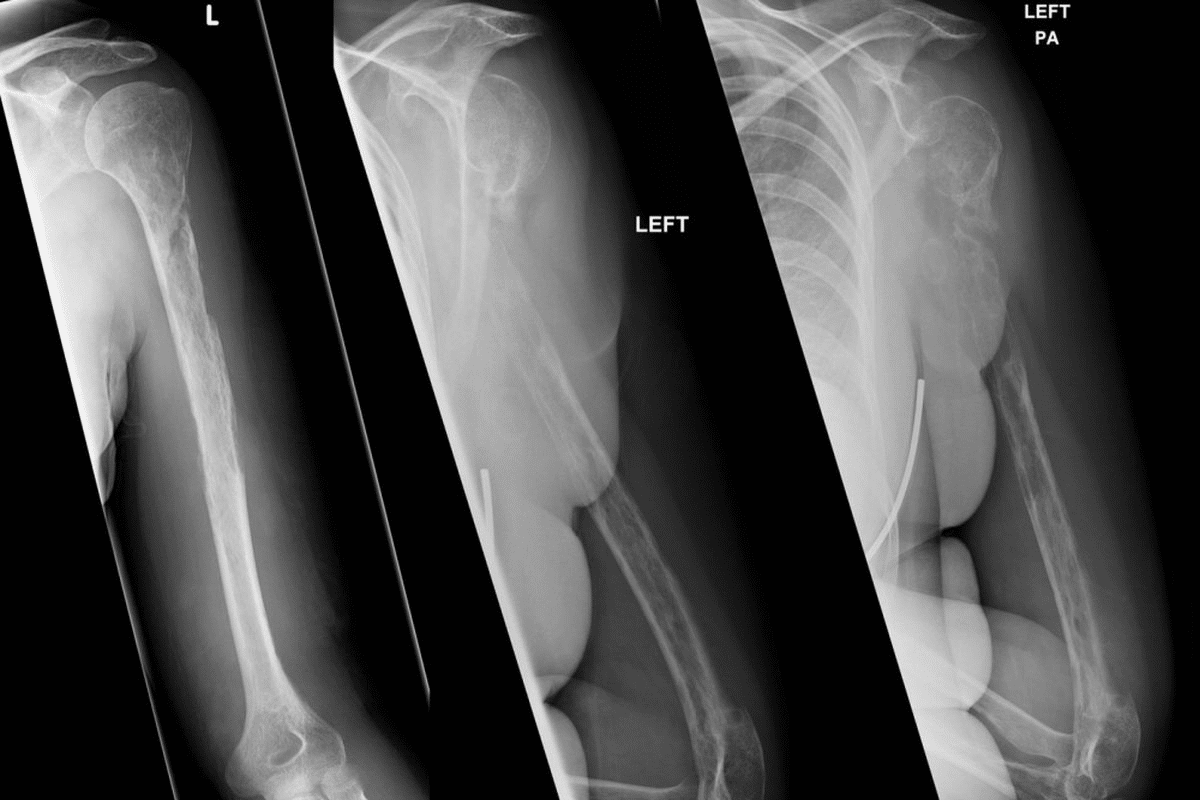

Imaging Studies: X-rays, DXA Scans, and Bone Markers

Imaging tests are key for checking bone health. X-rays help spot fractures or deformities. DXA scans measure bone density, which shows how healthy the bones are. Bone markers also help check bone health.

A leading expert says, “Imaging studies, like X-rays and DXA scans, are very important for diagnosing and managing Osteogenesis Imperfecta.” This shows how important these tests are in diagnosing the condition.

Surgical Interventions: Rodding and Correction of Deformities

Surgery is vital in managing osteogenesis imperfecta. Rodding is a common surgery where a metal rod is placed in the bone for support and to prevent fractures. This is very helpful for long bones like the femur and tibia.